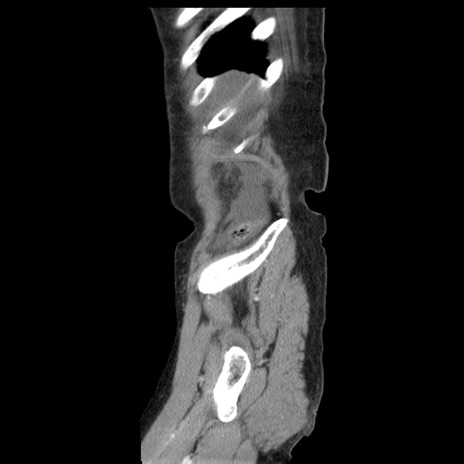

横断像

【症例】80歳代女性

【主訴】腹痛

【現病歴】8時間前から腹痛あり来院。

【既往歴】糖尿病、脂質異常症、子宮体癌にて子宮全摘術

【身体所見】意識清明・会話良好だが腹痛で苦悶様、全腹部にわたって反跳痛と圧痛あり

【データ】WBC 13600、CRP 0.14、LDH 224、CK 90